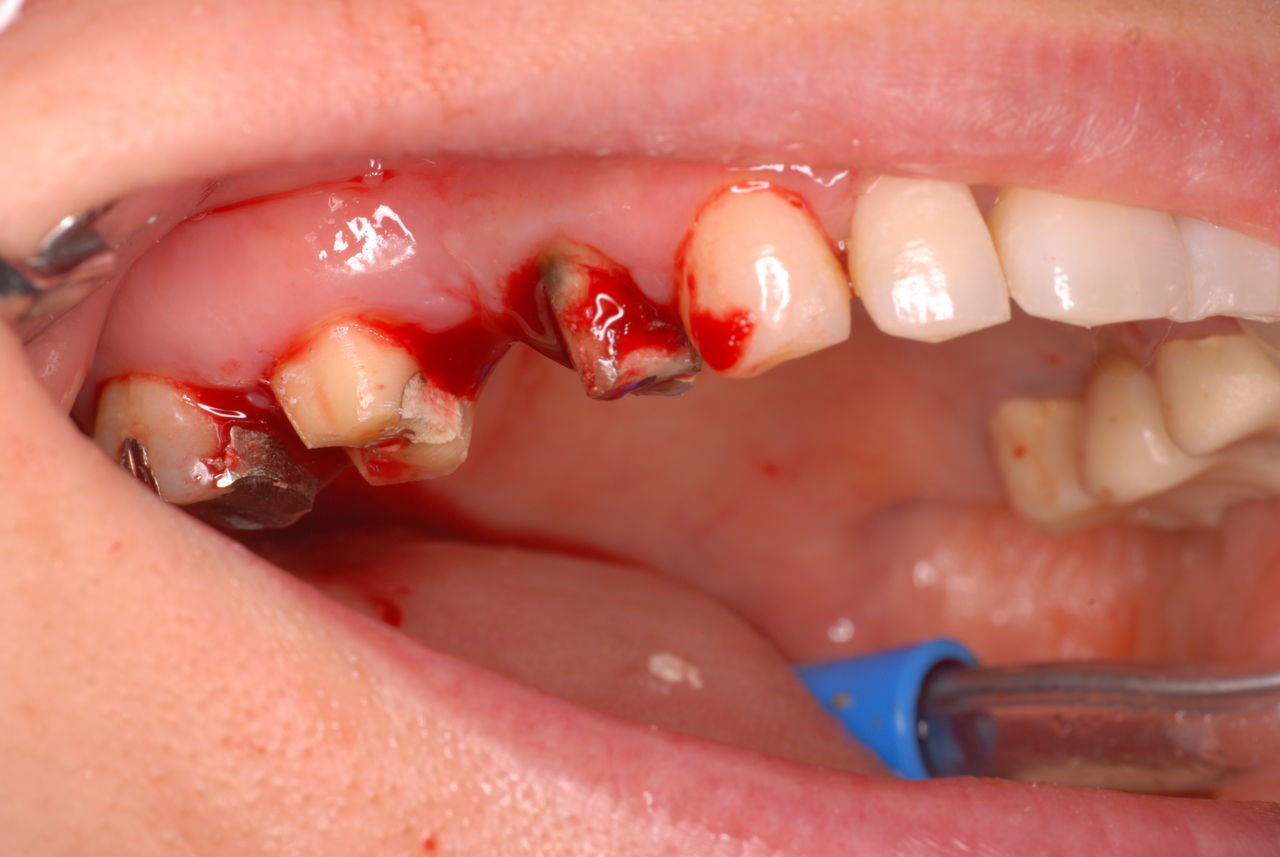

お口の中から差し歯、入れ歯、詰め物を追放しましょう!

口の中の病気を治し、病気を興さない医療を目指します。